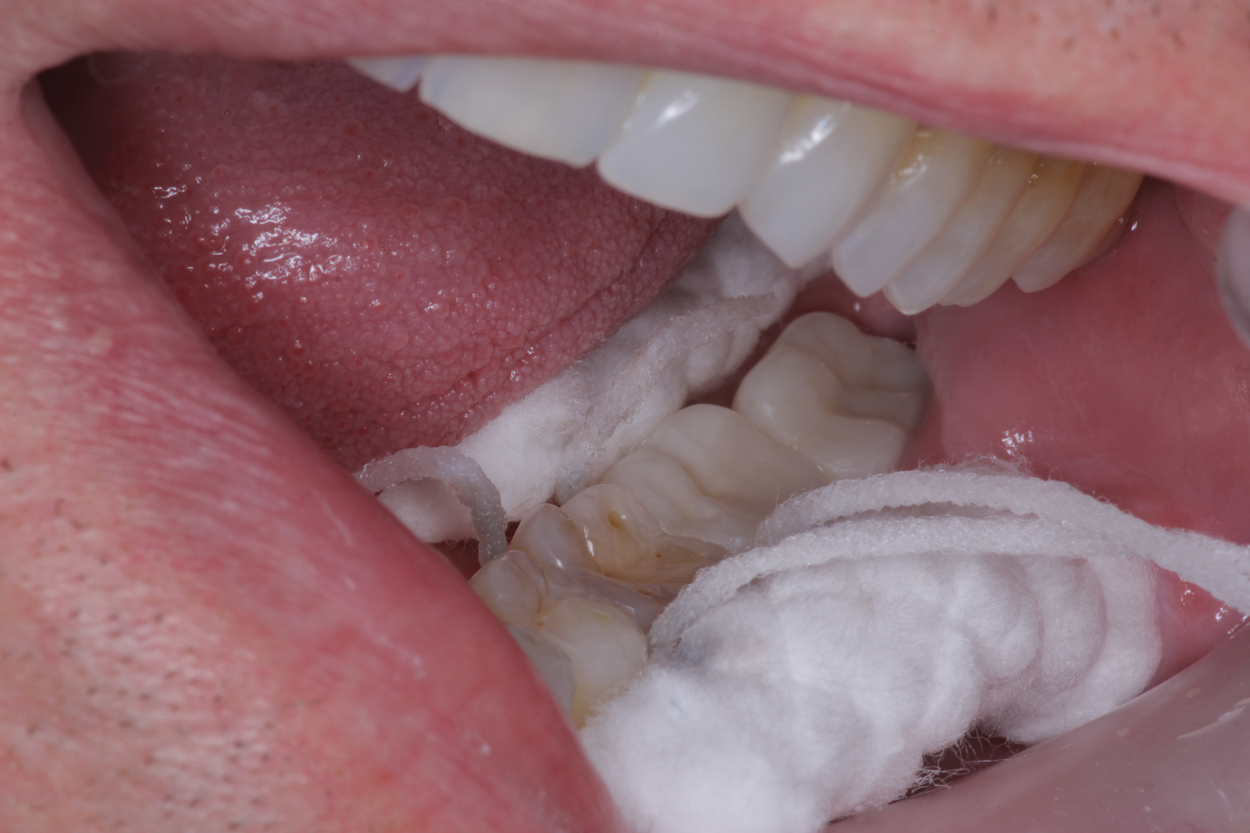

A 38-year-old female patient with incipient decay discovered on a transillumination caries detection device image (Figure 5 and Figure 6) presented for her bi-annual hygiene visit. The doctor was considering whether to treat the decay with a restoration or to "watch it." He decided that instead of monitoring the lesion, he could treat it with silver diamine fluoride, possibly halting the decay and hardening the lesion. The patient was informed of the possibility the decay would turn black; however, the decay process could halt, and she would not need a filling in the future. She was pleased at the prospect her tooth would remain intact without needing restorative treatment. After signing the consent form, she opted for treatment that day in the hygiene visit. She was appointed for one week later for the re-application of the silver diamine fluoride and advised that it may need to be reapplied one to two times per year.

(5.)  Incipient decay on tooth No. 29.

Figure 5

(6)  Incipient decay on tooth No. 20.

Figure 6